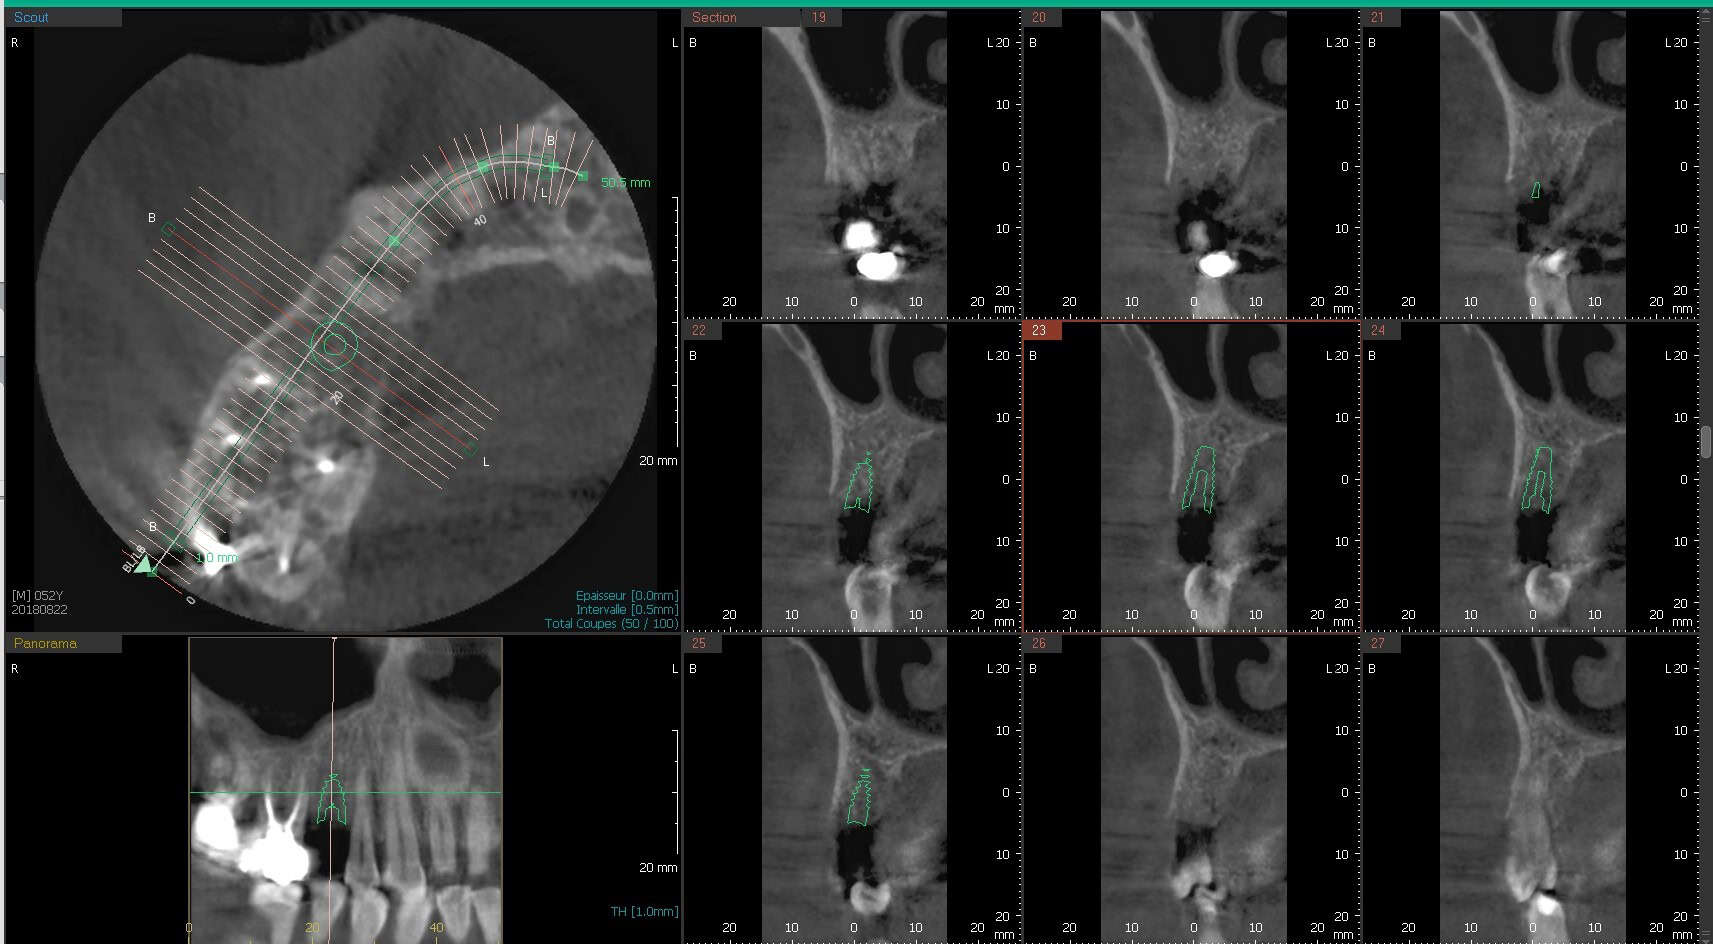

Exemple de cas :

les télécrânes pour l'orthodontie: